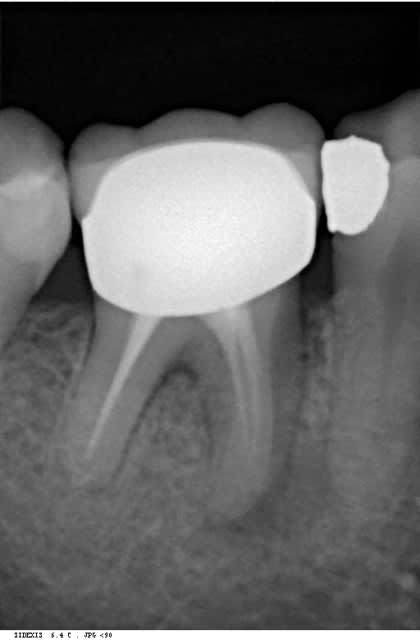

bon les pièces jointes d'alhoun.

décidément aussi nul en endo qu'en internet, et ton implant il est de traviole;)

Trev5 lavbuq - Eugenol

Trev1 rgpu7x - Eugenol

Trev2 c5sddm - Eugenol

Trev3 wgcbda - Eugenol

çà doit être une déformation du cliché, regardes bien le premier cliché avec le pilier de cicatisation: on voit bien la partie cylindrique puis l'évasement.